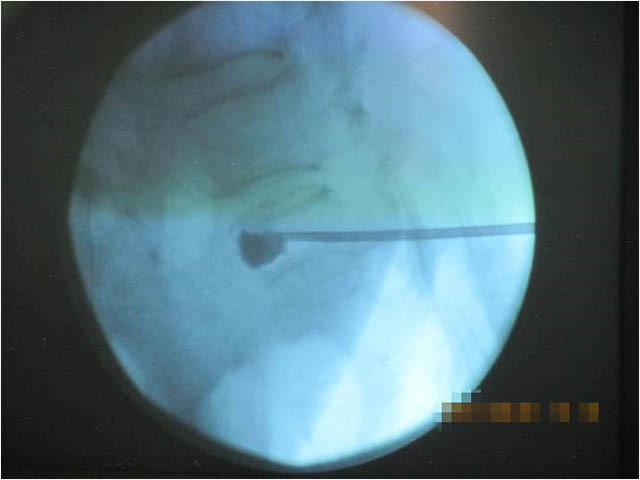

椎體成形術(shù)臨床全稱為經(jīng)皮穿刺椎體成形術(shù)(percutaneous vertebro plasty,PVP),屬于微創(chuàng)手術(shù),是通過向病變椎體內(nèi)注入骨水泥(聚丙烯酸甲酯,polymethylacrylate,PMMA)或人工骨達(dá)到強(qiáng)化椎體的技術(shù)。

通過在患者背部做一約2mm的切口,用特殊的穿刺針在X線監(jiān)護(hù)下經(jīng)皮膚穿刺進(jìn)入椎體,建立工作通道,將骨水泥或人工骨注入椎體內(nèi)穩(wěn)定骨折椎體,防止進(jìn)一步塌陷,明顯緩解疼痛。